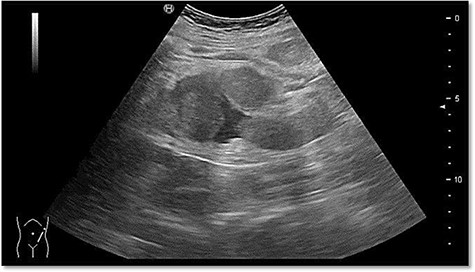

The ultrasound revealed some trace amount of free fluid in the left part of the abdomen (Fig. 1).

Abdominal sonography in the emergency department with free fluid on the left hemiabdomen.